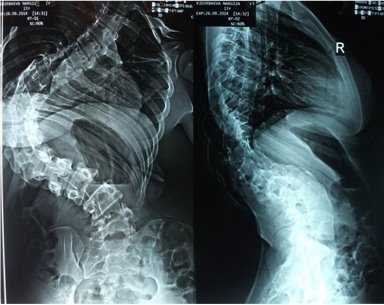

Клинический пример: больная Н., 1999 г.р., прооперированная по поводу сколиотической болезни (рис.1-4):

Рис. 2. Передняя и боковая спондилограмма до операции